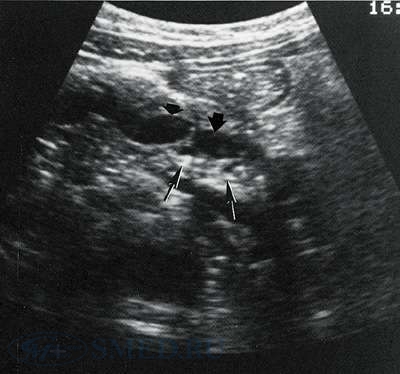

УЗИ-диагностика хронического панкреатита

На УЗИ определяется форма, величина, особенности эхоструктуры, контуры, состояние панкреатических протоков, кист или опухолей, состояние внутри- и внепеченочных протоков. Значительным плюсом служит возможность проведения УЗИ-диагностики в динамике.